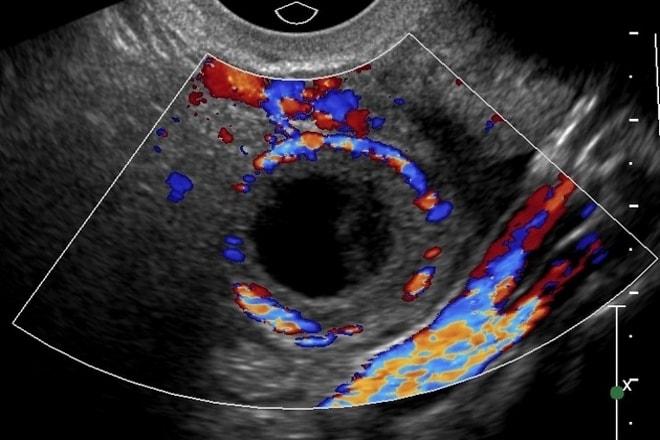

Анэхогенной называют такую структуру, которая способна поглощать и отражать ультразвуковые волны. Чаще всего она проявляется в виде кисты — новообразования округлой формы с утолщенными стенками. Внутри этой кисты скапливается жидкость, которая иногда может содержать примеси крови. Внутреннее содержимое новообразования характеризуется не только полной анэхогенностью, но и наличием сетчатой структуры с перегородками неправильной формы. Также могут наблюдаться гиперэхогенные включения.

При визите к врачу в первую очередь осуществляется анализ клинической картины заболевания и изучение истории болезни пациентки. Затем проводится гинекологический осмотр на специальном кресле. Если киста небольшого размера, врач может ее не заметить. В таком случае для постановки диагноза используется ультразвуковое исследование. Этот метод позволяет выявить новообразования различных размеров, а также определить их тип, расположение и структуру. Обследование выполняется через влагалище, что дает возможность ближе подойти к яичникам и получить более детальное изображение. На экране анэхогенная киста яичника отображается как темное пятно.